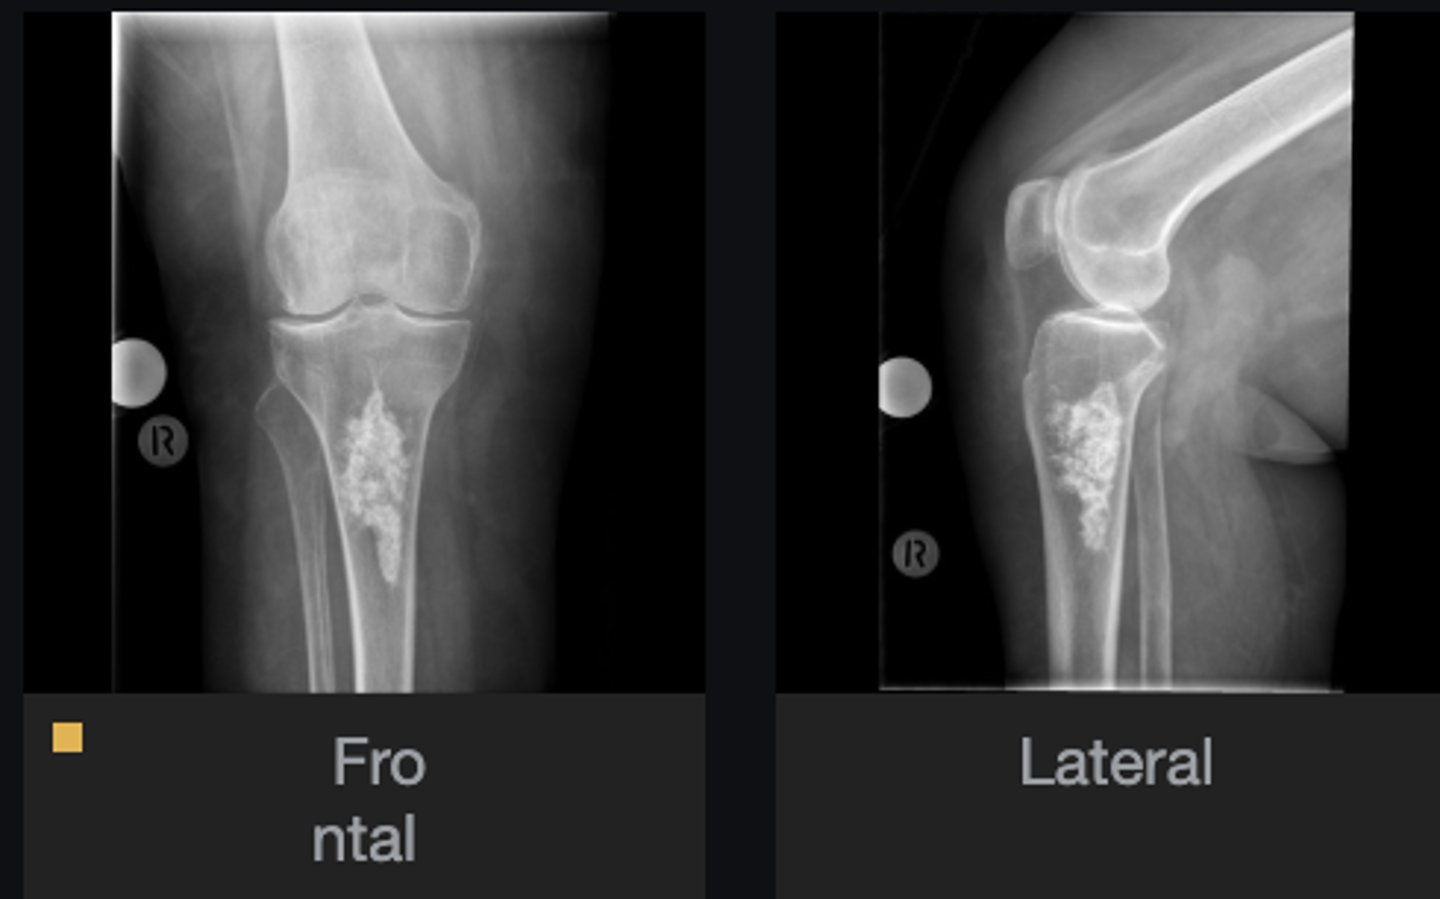

- Distal femur involved

- Elongated stalk

- Cortex and medulla are continuous

- Pointing away from joint

- Narrow base

Describe the bone lesion

<p>Describe the bone lesion</p>

Pedunculated solitary osteochondroma

Most likely diagnosis?

<p>Most likely diagnosis?</p>

- Fracture

- Malignant transformation (chondrosarcoma)

- Bursitis

- Neurologic injury

Concerns/complications?

<p>Concerns/complications?</p>

- Distal femur

- Metaphysis

- Anterolateral

- Broad base

- Cortex and medulla continuous

Sessile solitary osteochondroma